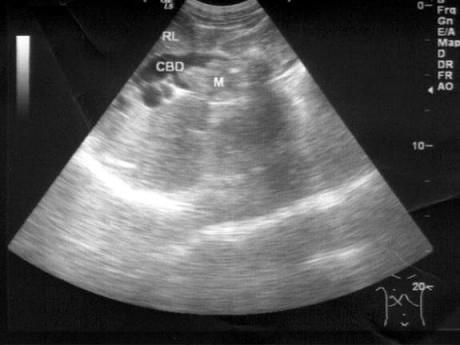

问题 患者女47岁,皮肤、巩膜黄染,进行性加重2个月余,腹痛、腹胀,既往有胆结石病史。B超检查如图所示,根据超声声像图,诊断为?(?)

选项 A.胆总管癌并结石 B.胆总管胆泥淤积 C.胆总管结石 D.胆总管蛔虫 E.胆总管癌

答案 A